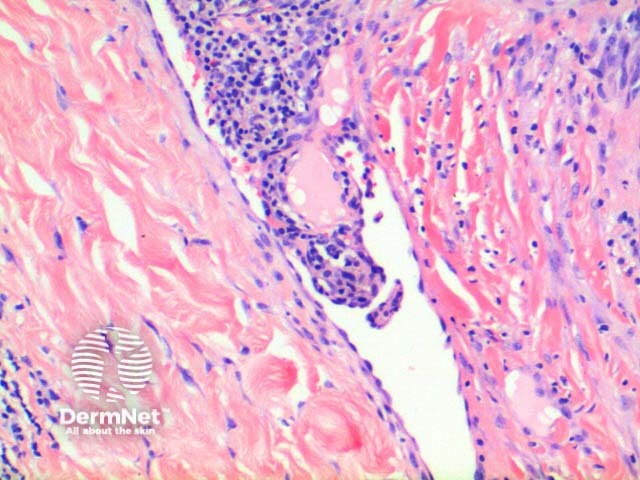

The low power view of the histology of Kaposi sarcoma is of a cellular dermal nodule (Figure 1). There may be varying degrees of overlying epidermal changes which can range from prominent hyperkeratosis and acanthosis to frank ulceration. The dermal proliferation is comprised of a spindle cell proliferation of endothelial cells forming sinuous vascular spaces. These may be sparse in patch phase lesions, progressing to fascicles of spindle cells in nodular lesions (Figures 2,3). This fascicular pattern has been likened to schools of fish. The spindle cells infiltrate through the collagen, forming slit-like spaces, especially towards the periphery of the lesions (Figure 4). Where the newly formed vessels project into an existing space the promontory sign is seen (Figure 5). This is now recognised as not being specific to this condition.

Figure 4

Figure 5